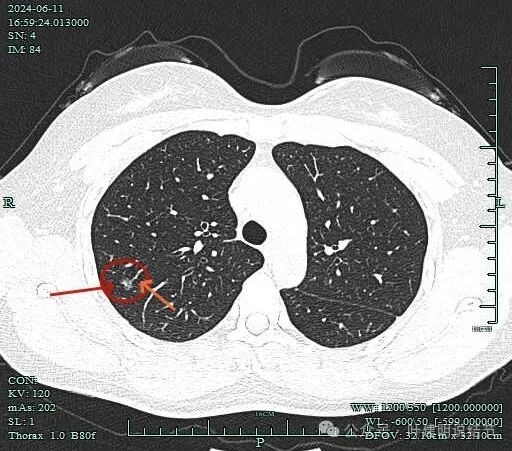

先看2024年6月的影像:

表面不平,有小血管进入病灶,病灶内部有点状偏高密度,整体轮廓清楚。